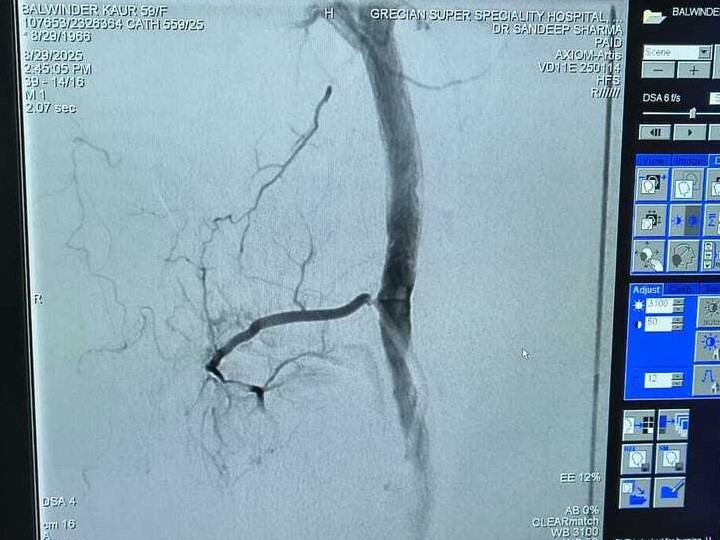

Balwinder Kaur Journey to Knee Pain Relief: A Successful GAE Treatment Story

Genicular Artery Embolization